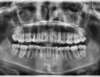

Rédicive d'un traitement dans l'enfance repris avec des gouttières

A-Début